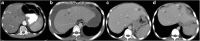

Objectives: We aim to illustrate the multimodal imaging spectrum of hepatic involvement in tuberculosis (TB). Whilst disseminated tuberculosis on imaging typically manifests as multiple small nodular lesions scattered in the liver parenchyma, isolated hepatic tuberculosis remains a rare and intriguing entity.

Methods: Indubitably, imaging is the mainstay for detection of tubercular hepatic lesions which display a broad spectrum of imaging manifestations on different modalities. While sonography and computed tomography (CT) findings have been described in some detail, there is a paucity of literature on magnetic resonance imaging (MRI) features. Due to a significant overlap with other commoner and similar appearing hepatic lesions, hepatic tuberculosis is often either misdiagnosed or labelled as indeterminate lesions. This article is a compendium of cases highlighting the spectrum of imaging patterns that can be encountered in patients with isolated primary hepatic tuberculosis as well as disseminated (secondary) disease. Rare patterns of primary disease such as tubercular cholangitis, hypervascular liver masses, and those with vascular complications are also illustrated and discussed.

Teaching points: • Hepatic TB has myriad imaging manifestations and is often confounded with neoplastic lesions. • Imaging patterns include miliary TB, macronodular TB, serohepatic TB and tubercular cholangitis. • Concurrent splenic, nodal or pulmonary involvements are helpful pointers towards the diagnosis. • Miliary calcifications along the bile ducts are characteristic of tubercular cholangitis. • Histological/microbiological confirmation is often necessary to confirm the diagnosis.